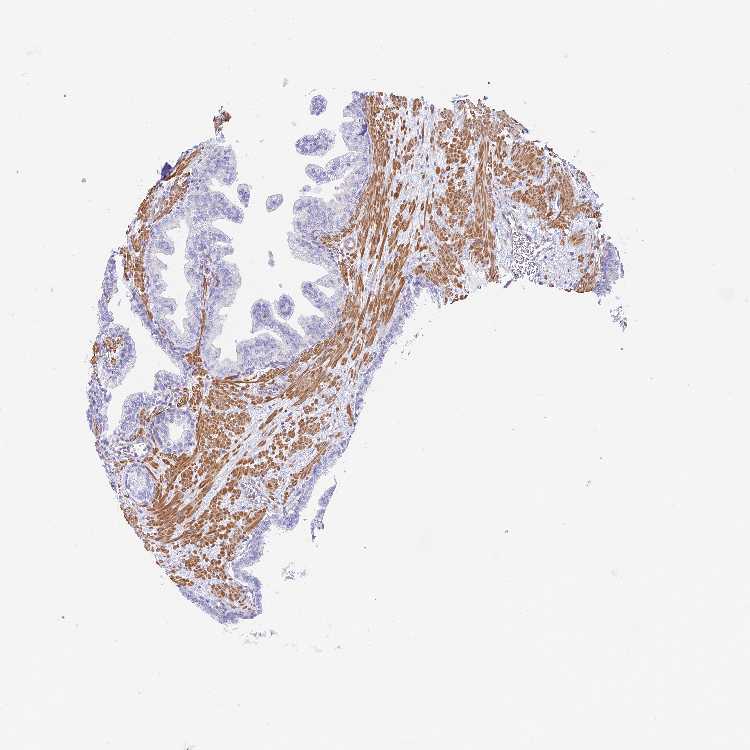

PROSTATE - Antibody stainingi

Antibody staining in the annotated cell types in the current human tissue is reported as not detected, low, medium, or high, based on conventional immunohistochemistry profiling in selected tissues. This score is based on the combination of the staining intensity and fraction of stained cells.

Each image is clickable and will lead to virtual microscopy that enables deeper exploration of all samples and also displays staining intensity scores, fraction scores and subcellular localization as well as patient and tissue information for each sample.

Antibody HPA040999Antibody CAB032656

Glandular cells Not detectedNot detected